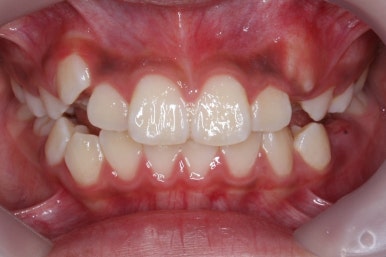

초진 시의 모습입니다.

11살의 어린이였기에 몇 군데 아직 유치가 남아있었습니다. 영구치가 모두 나오지 않았죠. 덧니가 있고 치열이 고르지 못하더라도 일반적으로 영구치가 더 나온 후에 연산동덧니교정 하는 것을 권해드립니다.

해당 환자분은 영구치가 아직 모두 나오지 않았지만 서둘려 교정을 시작한 이유는 2급 부정교합에 약간 가까웠기 때문입니다.

덧니 때문에 입다문 모습이 어색하고 턱끝에 힘이 들어가 복숭아씨치럼 쭈글쭈글한 모습을 보이고 있습니다.

덧니로 인해 웃을 때도 예쁜 모습은 아니네요.